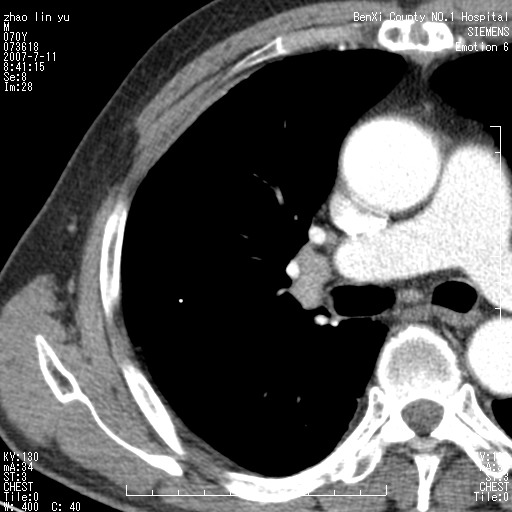

以下是引用王靖旗在2007-7-10 17:12:00的发言:[br] 男、70、咳嗽两个月,半年前换瓣手术,胸片未见异常,于昨天行x片发现右肺上野大片影,行ct扫描,这里是减薄图像,余肺正常。明天晚上会有增强扫描片,到时我会上传。[br][br] 冠状位请大家细看,应该是有意义的,[br][br] 请大家先看平扫发表意见。[br][br]

以下是引用zhangzhongshou在2007-7-10 21:43:00的发言:[br]右肺上叶周围型肺癌,以孤立型细支气管肺泡癌可能性大。